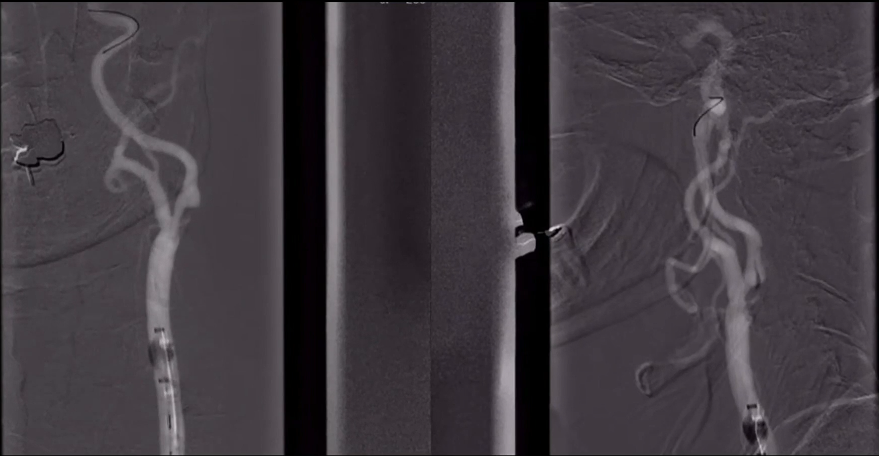

DSA:双侧颈内动脉起始部重度狭窄;前交通及双侧后交通未开放。

8F Fluxcap®球囊导引导管在5FMPA多功能125cm导管同轴辅助下送至右侧颈总动脉,微导丝送至C4段,沿微导丝送入6mm保护伞至C2段平直段,手推造影显示保护伞打开良好。

沿保护伞导丝送入4.0mm×30mm球囊,充盈球囊导引导管的球囊阻断血流,于狭窄段定位后命名压扩张球囊,泄球囊时在球囊导引导管的体外端予以负压回抽血液,取出一2mm血栓。经Fluxcap®球囊导引导管输送7.0-10.0mm×40mm自膨支架(Protégé RX)至狭窄段确认位置后释放。应用125cm多功能导管回收保护伞,多功能导管体外端予以负压回抽血液,保护伞内有血栓。

造影可见残余狭窄10%左右,颅内各分支血管通畅。